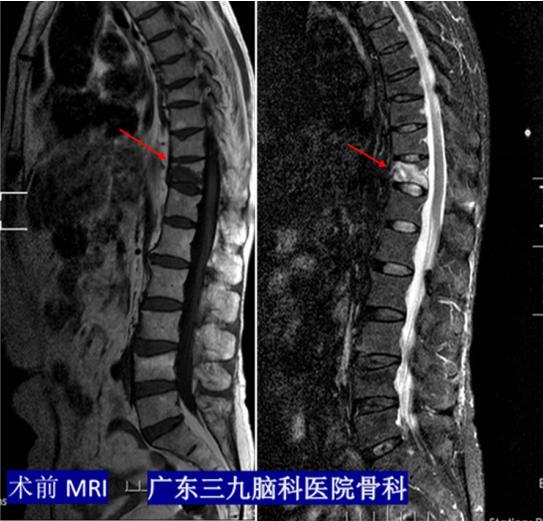

术前MRI:提示胸11椎体压缩性骨折并骨髓水肿,压脂相呈高信号

在查体过程中,王姐告知我院骨科柴亚胜主任,胸腰段脊柱叩痛明显,痛感向两侧腰部放射。另外,王姐的骨密度检查结果提示重度骨质疏松症;磁共振结果提示胸11椎体新鲜压缩骨折。王姐最终被诊断为胸椎压缩性骨折。

根据影像检查及查体,骨科团队就诊疗方案进行了讨论。柴亚胜指出:磁共振检查提示胸11椎体T2压脂呈高信号影,表明患者胸11椎体压缩性骨折属于新鲜骨折,而且症状明显,建议行微创手术解决疼痛。